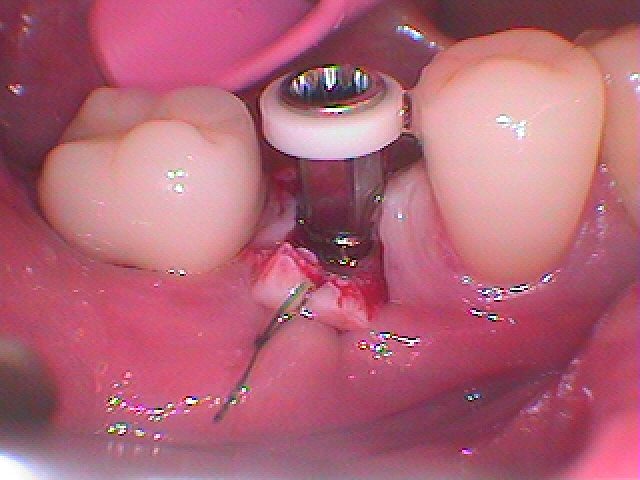

ここにインプラントを埋入していきます

角下歯肉がないのがわかります

口蓋側の死肉を頬側に持ってくる努力を行っていきます

このように開けていきました